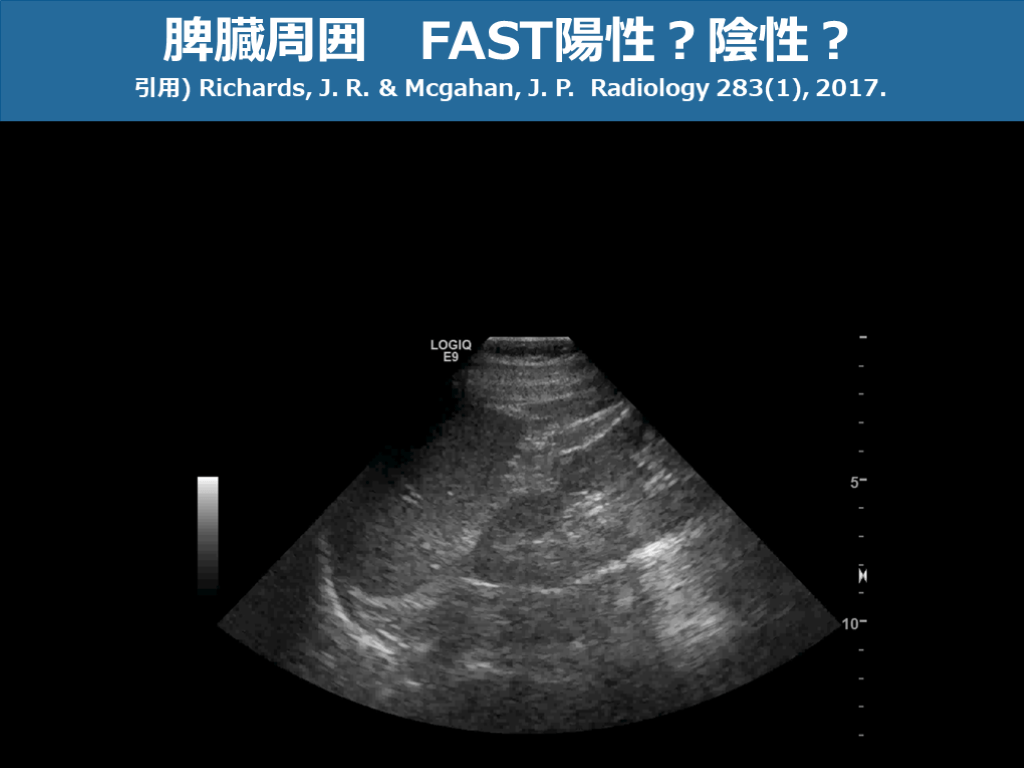

脾臓周囲 FAST陽性?陰性? 引用) Richards, J. R. & Mcgahan, J. P. Radiology 283(1), 2017. スライド画像)広島大学病院 演者作成

脾臓周囲 FAST陽性?陰性? 引用) Richards, J. R. & Mcgahan, J. P. Radiology 283(1), 2017. スライド画像)広島大学病院 演者作成 脾損傷+血腫を伴う液体貯留あり